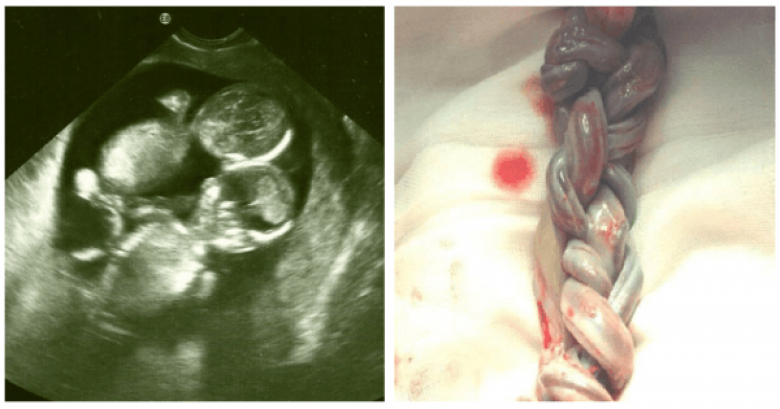

Настало время для первого УЗИ. Кейт, переполненная материнских чувств, абсолютно счастливая, отправилась к доктору. Уже давно знакомый для ее семьи медик шутит: «Может у тебя там снова двойня?» Как в воду глядел! В утробе Кейт действительно билось два сердца. Но эта новость, к сожалению, была не единственной на тот день.

Эмбрионы разделились только после 8-13 дней осеменения. Это означало, что между двумя детьми не было защитной мембраны. Через пару дней дети могли бы стать сиамскими близнецами. Но это еще полбеды! При подобной монохориальной беременности пуповина одного ребенка могла запутаться о другого, вызывая риск удушения малыша. Шанс на жизнь у этих близнецов не составлял больших процентов.

Врач советует Кейт не беспокоиться, держать все в секрете и позволить природе взять верх… Но какая мать смогла бы так поступить? После двадцати восьми недель беременности эта женщина проводит тридцать пять дней в больнице, сражаясь каждый миг за жизнь своих малышей. При родах ей делают кесарево сечение. Когда доктора увидели пуповину, в комнате воцарилась мертвая тишина.

Обе пуповины были плотно переплетены, как косичка! Трудно было поверить в то, что девочки выжили. Но это еще далеко не все.